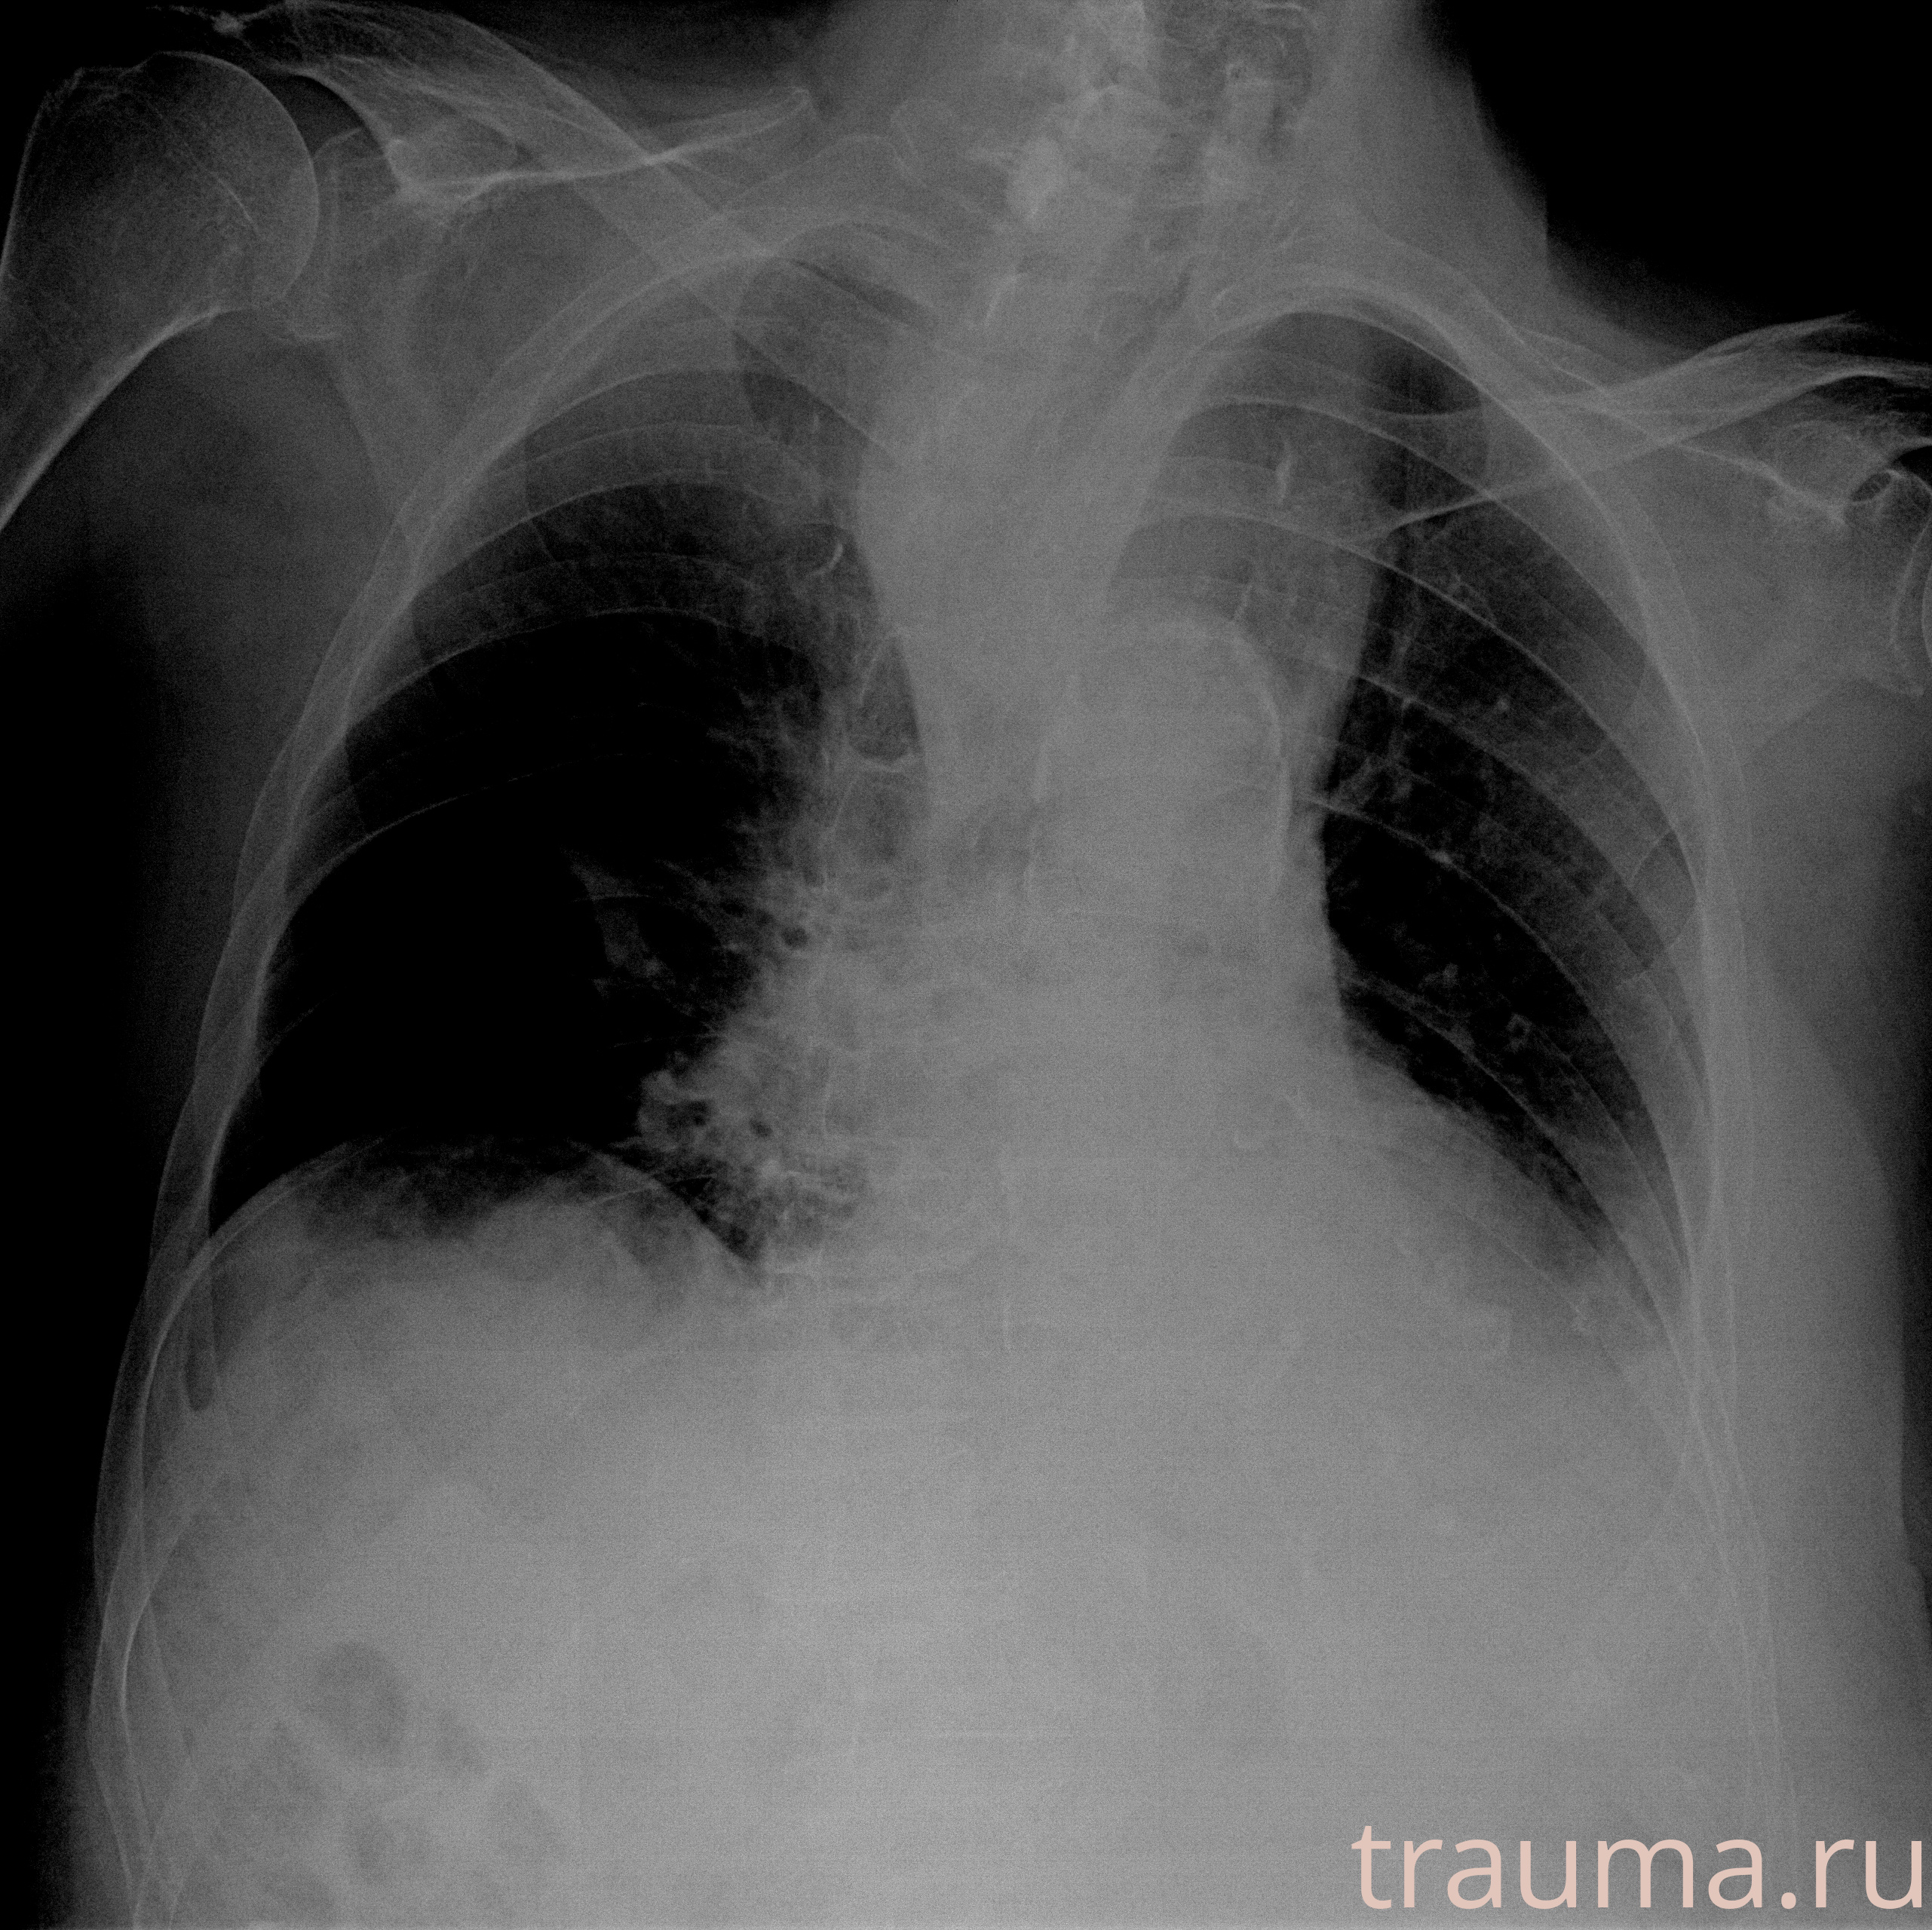

Рентгенограммы

Рентген на дому: по вашему адресу приезжает врач-рентгенолог, травматолог-ортопед с мобильным рентгеновским аппаратом, проводит диагностику травмы или заболевания, делает необходимые рентгенограммы, дает рекомендации по дальнейшему лечению. Получить качественные снимки в домашних условиях возможно благодаря уникальной методике, разработанной МосРентген Центром для института  Склифосовского

при переломе шейки бедра и пневмонии от компании МосРентген Центр - партнера Института имени Склифосовского